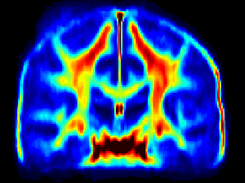

Normative myelin water atlas was created by co-registering and averaging myelin images in MNI space from 50 healthy brains to depict the population mean and variability of the myelin content in the brain. The myelin images of individual subjects were acquired using myelin water imaging. Details about myelin water imaging technique and its analysis can be found here: https://mriresearch.med.ubc.ca/news-projects/myelin-water-fraction/. The created myelin water atlas with its standard deviation can be used as a reference for your own studies related to myelin. A full description of this work can be found in this paper: https://www.ncbi.nlm.nih.gov/pubmed/31347238.

• Myelin water imaging

• Atlas for normal myelin content